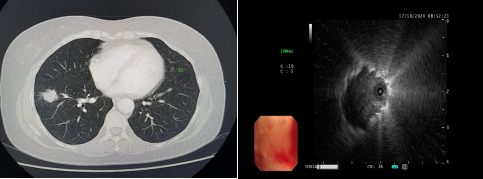

患者,女性,于10天前无明显诱因出现咳嗽,干咳为主,未予以重视,之后仍咳嗽、咳痰,就诊于外院,胸部CT提示双肺纹理增粗、右肺门团块影、右肺下叶前基底段实性结节团。为求进一步诊治转入我院乐鱼在线登录入口。入院后完善相关检查,于10月17日9时安排气管镜检查,副主任医师韩蓓与主管护师薛冬冬为患者行气管镜检查,镜下示:双肺支气管均未见明显异常,结合CT给予超声探查,于右肺下叶前基底段亚支探及偏心异常回声区,由于亚支位置较远且管腔较窄,活检钳无法到达,给予冷冻肺活检,成功获取3块活检标本,活检病理结果提示为恶性肿瘤。